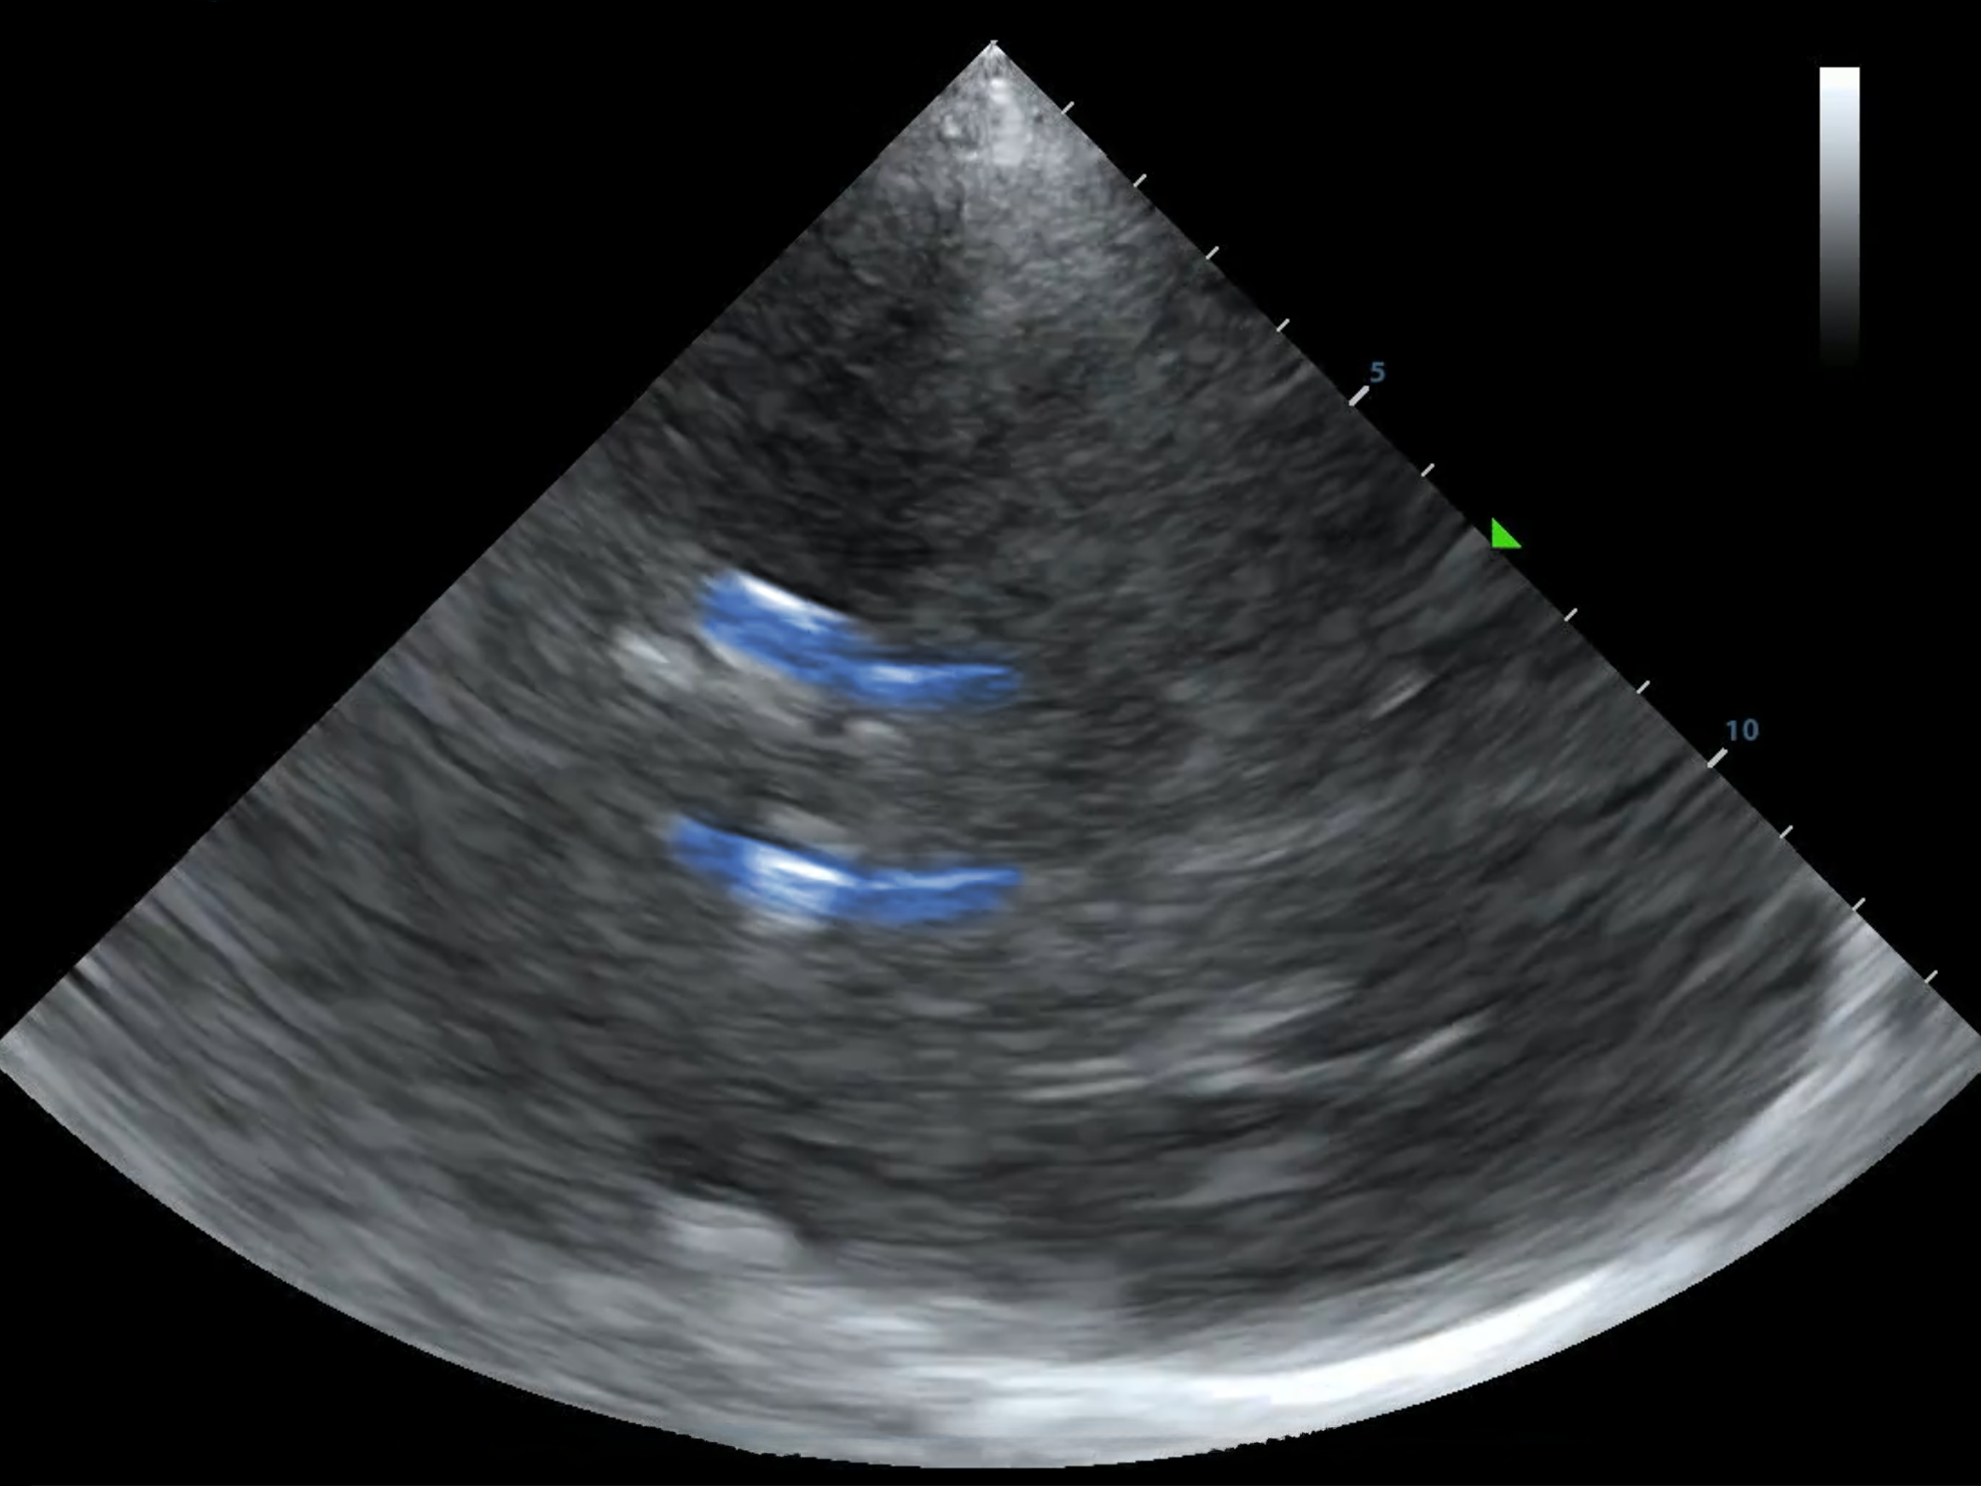

This is the Diencephalon Plane, where the dark thalami surround that sweet, sweet third ventricle like a rain cloud.

This is also where the Circle of Willis lives. But practice getting here first--finding the third ventricle can be challenging.